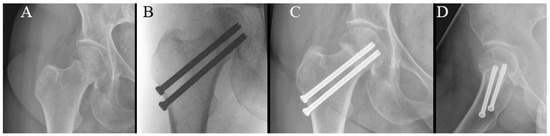

Figure 5.

Radiographs of cannulated hip screw fixation with three screws. (A) Preoperative radiograph. (B) Perioperative radiograph. (C) Anteroposterior radiograph at 6-week follow-up. (D) Lateral radiograph at 6-week follow-up.